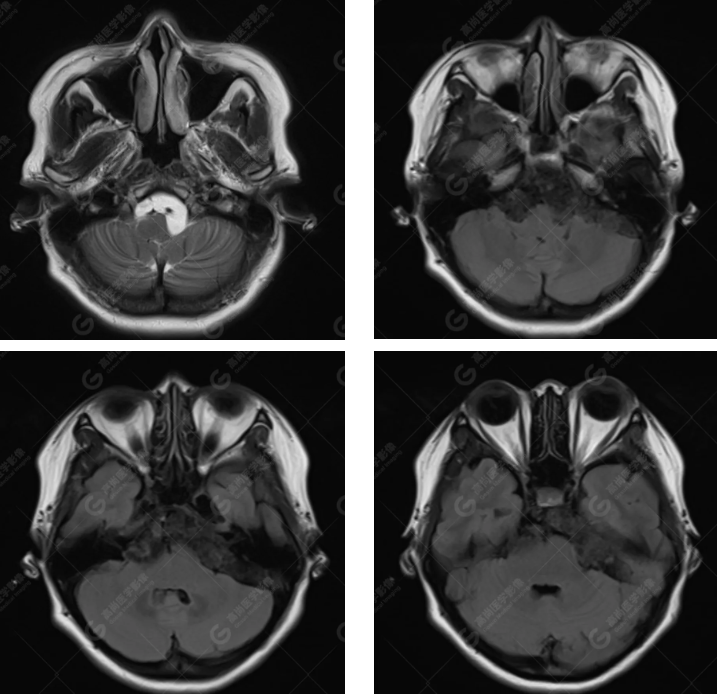

MRI 影像所见:

延髓池、桥前池、双侧桥小脑角区、鞍上池至左侧小脑幕下见团片状异常信号影,呈长 T1 长 T2 信号,FLAIR 序列呈不均匀稍低信号,DWI 序列呈高信号,ADC 图低信号,增强后无强化。右侧面听神经受压向后移位,双侧三叉神经及左侧面听神经被包埋,显示不清。

延髓池、桥前池、双侧桥小脑角区、鞍上池至左侧小脑幕下胆脂瘤,右侧面听神经受压向后移位,双侧三叉神经及左侧面听神经被包埋